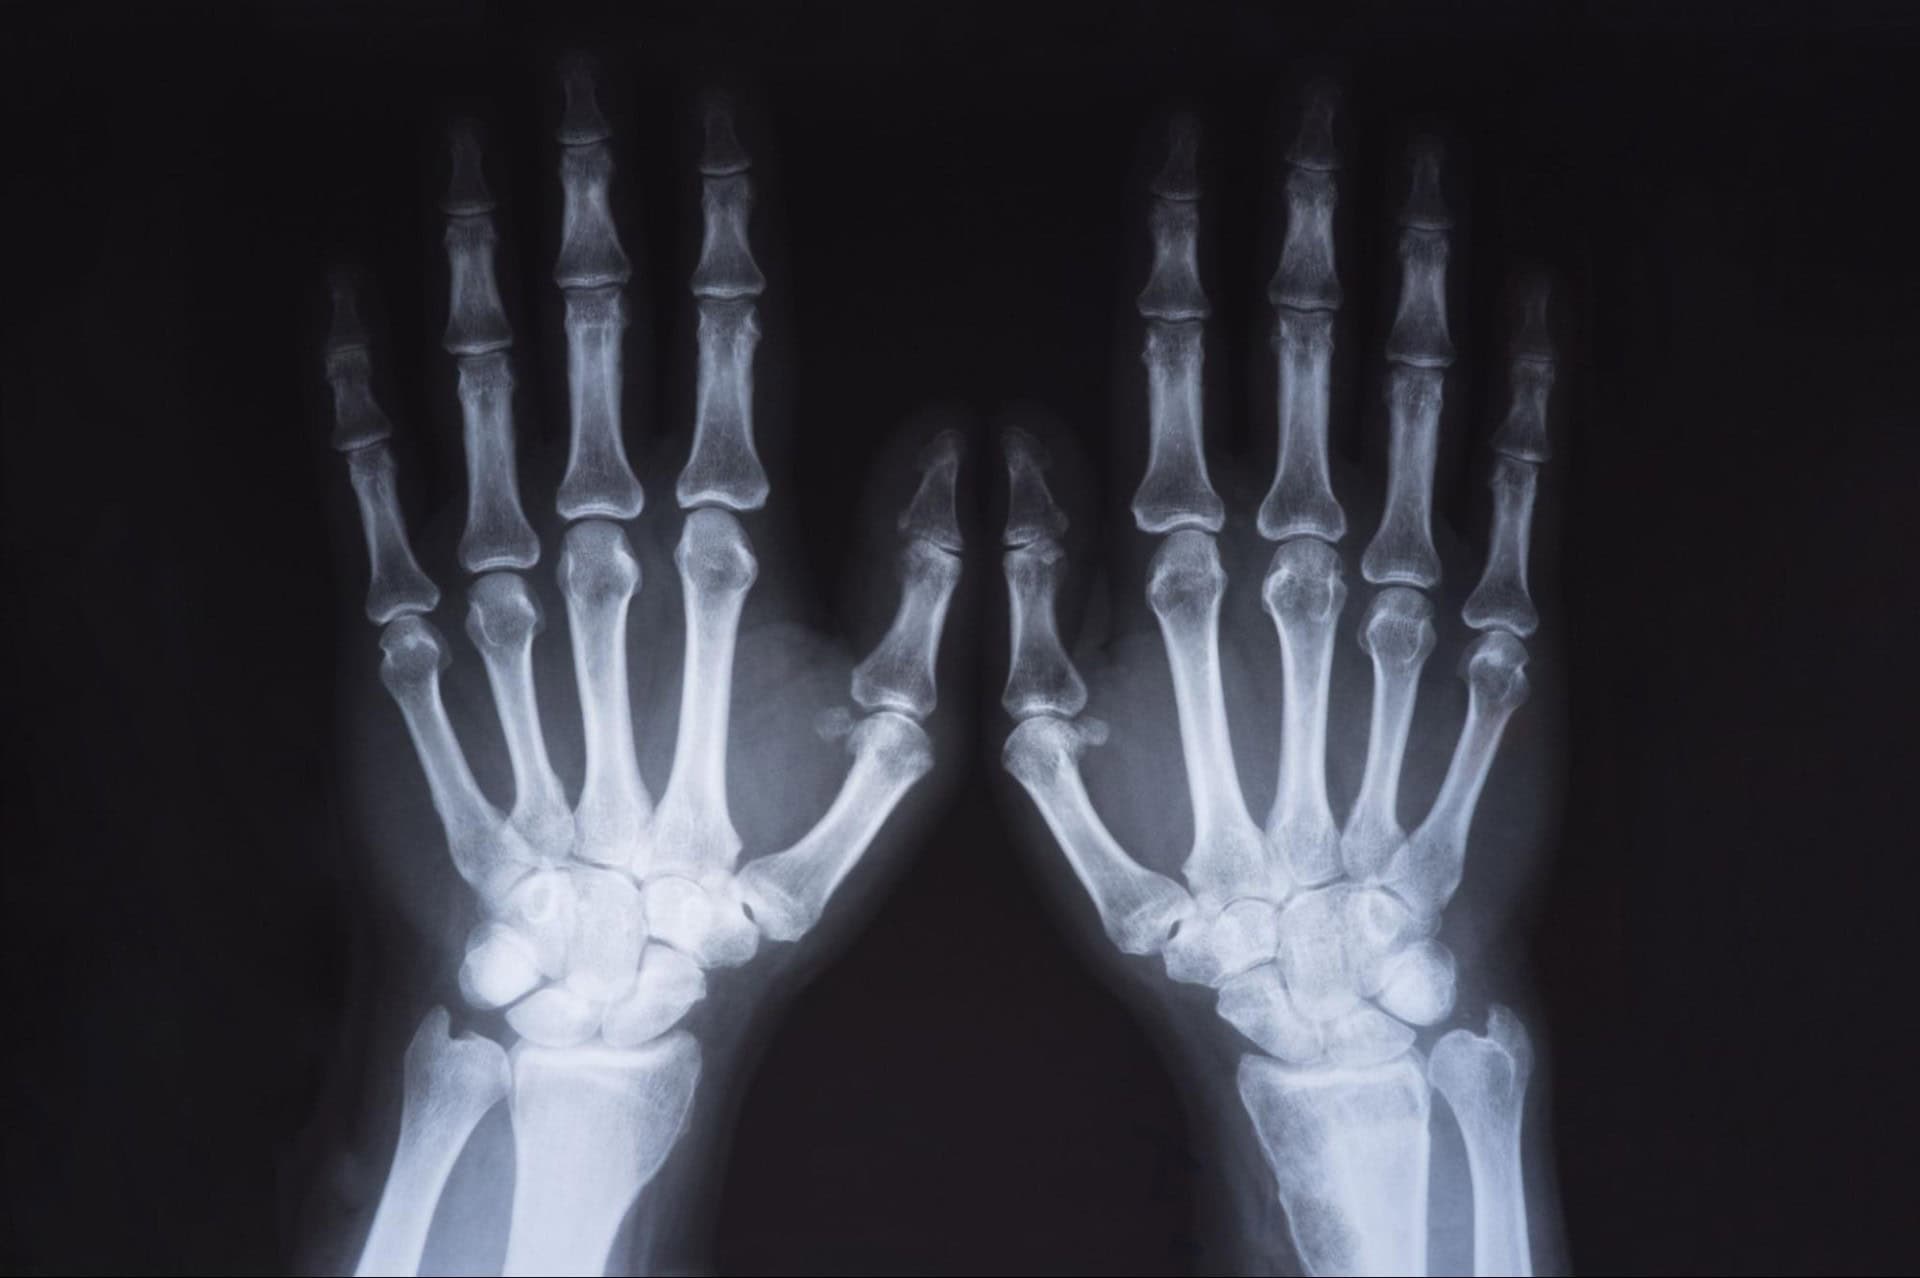

There are 27 bones in the hand and wrist. With 14 finger bones, 13 bones that extend from the palm to the wrist, and a network of soft tissue and joints that connect them, it can be challenging to tell the exact cause of wrist pain after a car accident. Consider the anatomy of both structures to better understand where your injury might be located, and visit a medical professional to know for sure.

The hand is primarily composed of 14 finger bones, medically known as phalanges. Phalanges are connected to the inside of the palm by five bones called metacarpals. There are eight other bones inside the palm called carpals, which connect the hand to the wrist.

There are 27 joints in the hand connected by bands of soft tissue called ligaments. In addition to ligaments, soft tissues called tendons keep the rest of the hand bones together and connect muscles to bones. The hand is also home to a web of nerves, which communicate with the brain to dictate movement.

The eight carpal bones of the hand are joined by two arm bones, the radius and ulna, to form the wrist. There are three wrist joints: the radiocarpal joint, ulnocarpal joint, and distal radioulnar joint. Thick bands of ligament support these joints, protecting the flow of nerve communication between the brain, arm, and hand.

A motor vehicle accident can partially or entirely break any bone in the hand and wrist. For example, a broken phalanx is a type of hand fracture in a finger bone. A carpal bone fracture is a wrist fracture in the bone that connects the hand to the wrist.

Treatment for hand and wrist injuries after a car accident begins with an accurate diagnosis. A medical professional can complete X-rays or an MRI scan to diagnose the injury. Once accurately diagnosed, a few common treatments for a hand and wrist injury include: